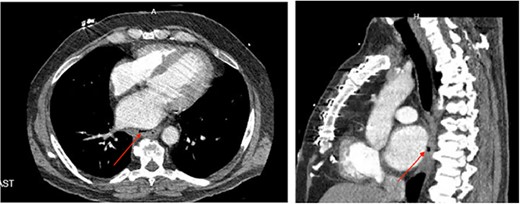

A 58-year-old man, who underwent a left atrial ablation for atrial fibrillation, presented to an outside hospital 4 weeks post-ablation with quadriparesis, chest pain, and fever. A non-contrast CT of the brain revealed infarcts with pneumocephalus. Given his recent ablation, a CT chest was performed, demonstrating a pericardioesophageal fistula (Fig. 2a and b). The patient was started on broad-spectrum antibiotics and was transferred to our institution and taken emergently to the OR, where he underwent a left thoracotomy. Once the pericardium was entered, two small defects in the left atrium were noted, indicating that the atrium was involved in the fistula. These were repaired primarily. Inspection of the esophagus revealed a 3 cm defect, which was also repaired primarily. An intercostal muscle flap was placed between the esophageal repair and the pericardium. During his hospitalization, he had multiple pulseless electrical activity cardiac arrests and a declining neurologic exam. Despite multiple CT scans and esophograms revealing a solid repair with no evidence of a leak, he continued to appear septic, likely due a small, persistent atrioesophageal fistula undetectable by imaging. Following his last arrest, his neurologic status declined significantly, and the decision was made to transition to comfort care, and he subsequently expired.

(a) Axial CT image of pericardioesophageal fistula of Case 4 (arrow indicates area of fistulization); (b) sagittal CT image of pericardioesophageal fistula of Case 4 (arrow indicates area of fistulization).